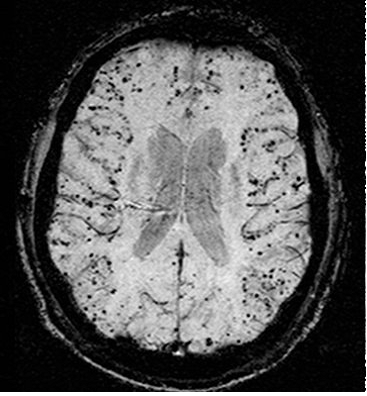

뇌 속 치매 덩어리(검은 점·아밀로이드 단백질)

뇌세포(청색, 자색) 사이사이 노폐물(황색·아밀로이드, 타우)이 청소되지 못하고 만성염증을 일으켜 뇌세포를 죽인다.